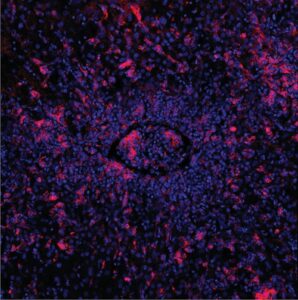

Mehr erfahren zu: "Behandlungen mit selbst hergestellten CAR-T-Zellen zeigen Erfolg bei Krebs und Autoimmunerkrankungen" Behandlungen mit selbst hergestellten CAR-T-Zellen zeigen Erfolg bei Krebs und Autoimmunerkrankungen An der Medizinischen Universitätsklinik Tübingen ist es gelungen, zwei Patienten mit besonders therapieresistenten Leukämie-Erkrankungen mit einer neuen Form von CAR-T-Zellen erfolgreich zu behandeln. Die CAR-T-Zellen sind vermutlich besonders wirksam, weil […]